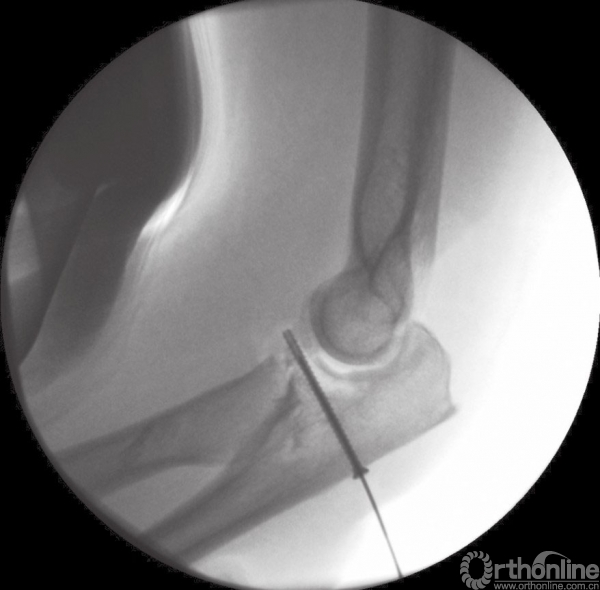

对于这种复合损伤,桡骨头切除术是禁忌的。骨折块可以通过克氏针临时固定,或者使用复位钳钳夹复位,再用微型螺钉进行固定(图6)。如合并桡骨颈骨折,可以使用克氏针临时固定后再用微型T型钢板进行固定。

图6 间接复位冠状突骨折块